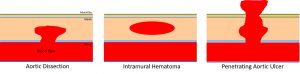

A penetrating aortic ulcer is somewhere on the spectrum between an intramural hematoma and an aortic dissection. It is a focal disruption of the intima and elastic lamina into the media.

Penetrating aortic ulcers are usually an incidental finding on CT or MR. On CT look for contrast that is separate from the main aorta channel. An ulcer is sometimes hard to distinguish from an ulcerated plaque. An ulcerated plaque is actually not considered part of the “acute aortic syndrome” spectrum (it is more in line with a “regular” atherosclerotic process. I recommend reviewing images with vascular radiology. Doing so has helped me in the past. One differentiator is if contrast goes beyond the diameter of the aorta. Contrast outside the diameter denotes an ulcer (so, yes, the example in the picture below is not a perfect one):